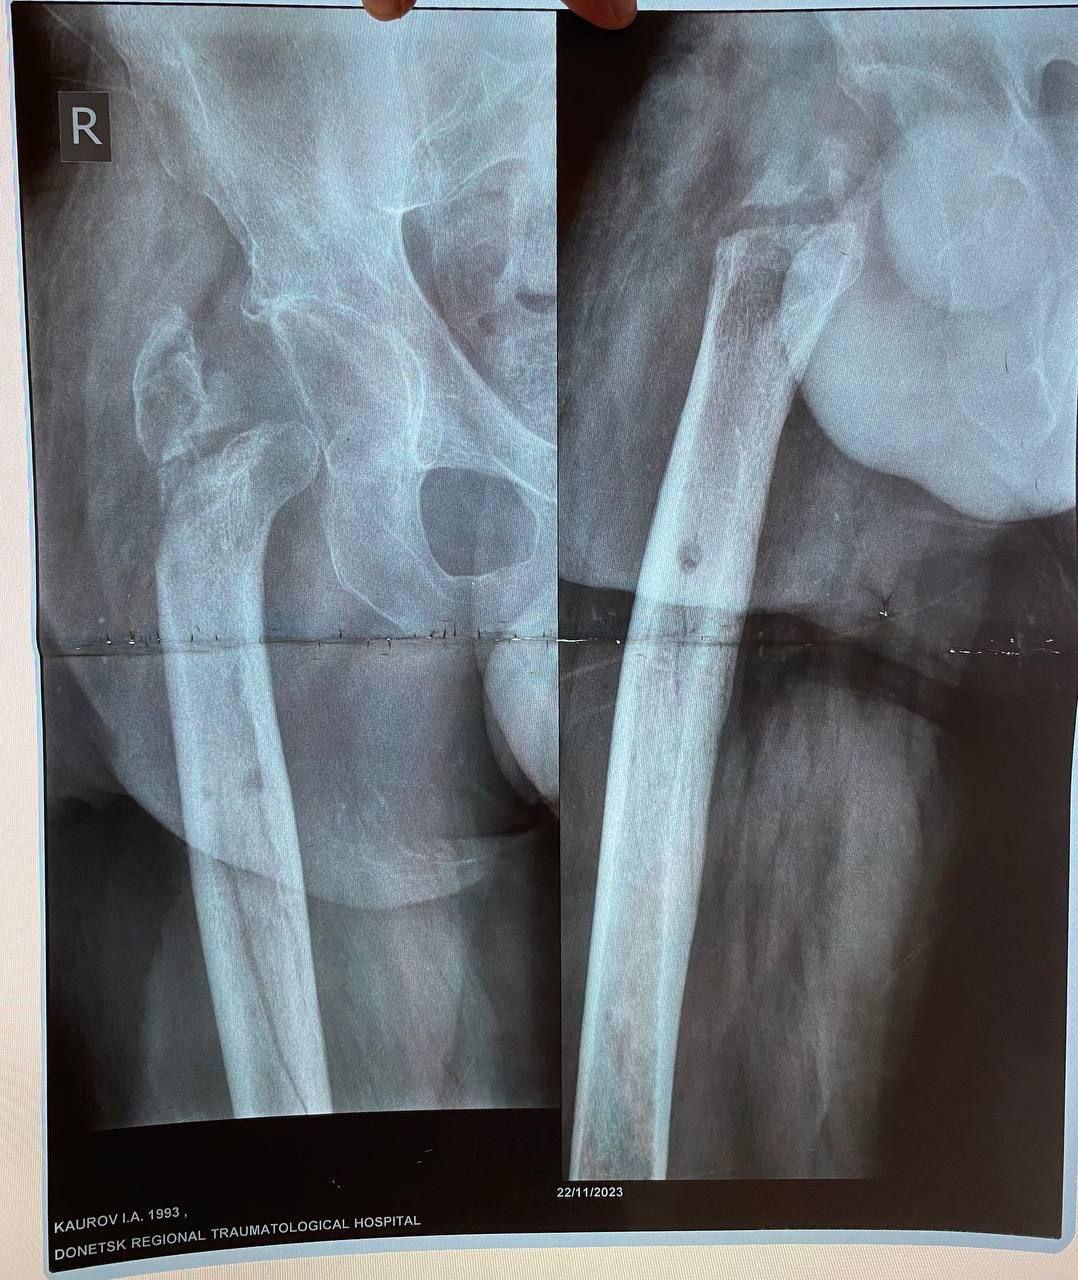

Мобилизованный 25 февраля 2022 года, военнослужащий прошел через горнило Херсонщины. 28 августа 2022 года в 23:10 под ракетным обстрелом боец получил тяжелейшее ранение правого бедра. В июле 2024 года сержант, удостоенный медали «За отвагу», был уволен со службы по состоянию здоровья.

Из-за обширных повреждений и многократных операций правая нога бойца стала короче левой на восемь-девять сантиметров. Обычное эндопротезирование изменить ситуацию не могло.